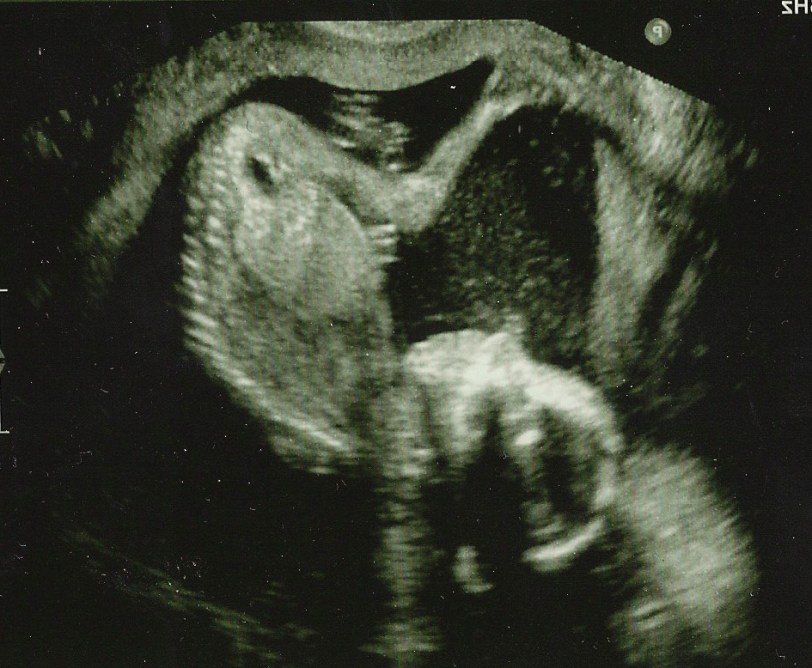

Meanwhile, I have exciting news to share, which I hope makes up for my long absence! Adam and I are now the proud parents of this little guy:

That’s right! We’re having a baby. I’m currently five months pregnant and feeling great! The pregnancy has been quite smooth thus far – absolutely zero morning sickness, energy’s remained pretty high and as far as we know – baby is doing swimmingly. For the most part, I haven’t been turned off or turned on by any weird foods – actually… just milk. I’ve been craving tall glasses of cold milk, which is definitely a new thing for me. Though you all know my obsession with dairy products, so I guess it’s just heightened a bit. Other than that, I’ve been eating like I always eat – while trying to keep it a little healthier by cooking more and adding in extra fruits and veggies.

In this ultrasound photo the little babe’s chilling upside down. He looks pretty happy – sort of looks like he’s smiling right? And just look at that spine and those skinny little legs! CRAZY! At our twenty-week scan last Wednesday we saw him sucking his thumb and just this past week I’ve started feeling him moving around a little. What a trip.